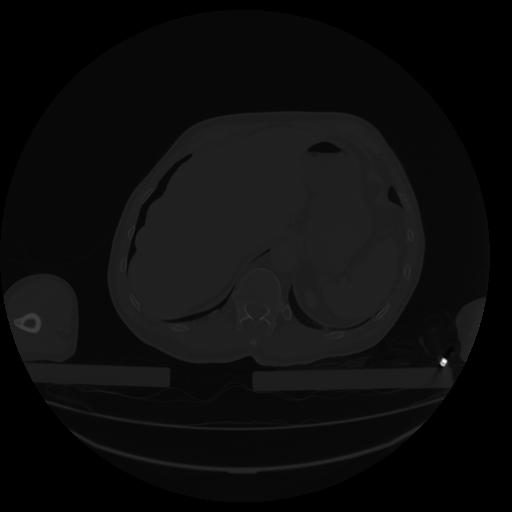

34 CUERPO,CE,Vol,1.0,CUERPO,,